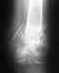

Накачивание мышц не спасет, проблема в деформации головки плеча и суставной впадины лопатки. Надо думать об операции.